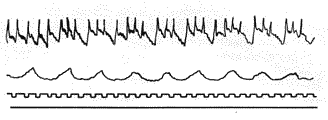

Сфигмография. На аппарате И. Г. Шарабрипа можно проводить запись артериального пульса у собак. Как указано было выше, графическая запись артериального пульса дает наглядное представление о частоте, ритме и характере пульсовой волны. Графическую запись пульса у собак проводят по двум артериям: по бедренной и плечевой.

Нормальная сфигмограмма у собак состоит из двух колен: быстро восходящего, короткого и нисходящего, слегка наклонного и более длинного, чем восходящее. На нисходящем колене имеется приподнятость, носящая название дикротической волны. Восходящее колено соответствует систоле левого желудочка, по конец систолы распространяется еще на некоторую часть нисходящего колена, и конец систолы лежит где-то на нисходящей кривой; следовательно, нисходящее колено соответствует концу систолы и всей диастоле. Сфигмография может быть использована для функционального диагноза при расстройстве кровообращения и для изучения терапевтического воздействия лечебных препаратов (рис. 4).

Кривая одновременной записи пульса и дыхания у собаки. На сфигмограмме отчетливо видна респираторная аритмия: во время фазы вдоха пульс учащается, во время фазы выдоха пульс становится редким